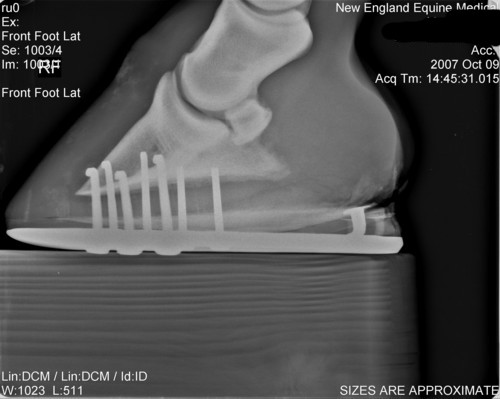

Here are his xrays from about 10-12 weeks ago after the first corrective shoeing. Also included picture of his feet last year before any problems.

Last year

Left AP

Left lat

Right AP

Right Lat

Though I will measure it later, the coffin bone' solar surface angle is acceptable as shod and it should be noted this value does vary greatly among normal horses. Note this is not the same as saying there has been no rotation since the farrier has adjusted the angle with a pad and could have rasped the front wall parallel. We just do not have the information to judge.

Breakover, which is about a cm or two in front of the tip of the coffin bone, looks pretty good though I would prefer a lot more slope to the rocker like that seen in a natural balance shoe. The breakover point of these shoes would disappear on soft ground as the shoe sinks and breakover moves forward to the tip of the foot. Julie would then be right with breakover well too far forward.

Although these images demonstrate the lack of heel and the attempts to correct it, at least the appearance 60 days ago, I would still like to see current images of the foot and sole itself. Your old farrier is correct if the horn quality of the wall is poor and/or the wedges overload the heels. The wedges will distort and breakout poor quality horn and pressure overload slows the growth of the wall at these points. I also do believe egg bars help support poor quality heels when used with proper trimming principles and horn care for more on the trimming see Diseases of Horses » Lameness » Diseases of the Hoof » Correcting Long Toe Low Heel Foot Conformation.